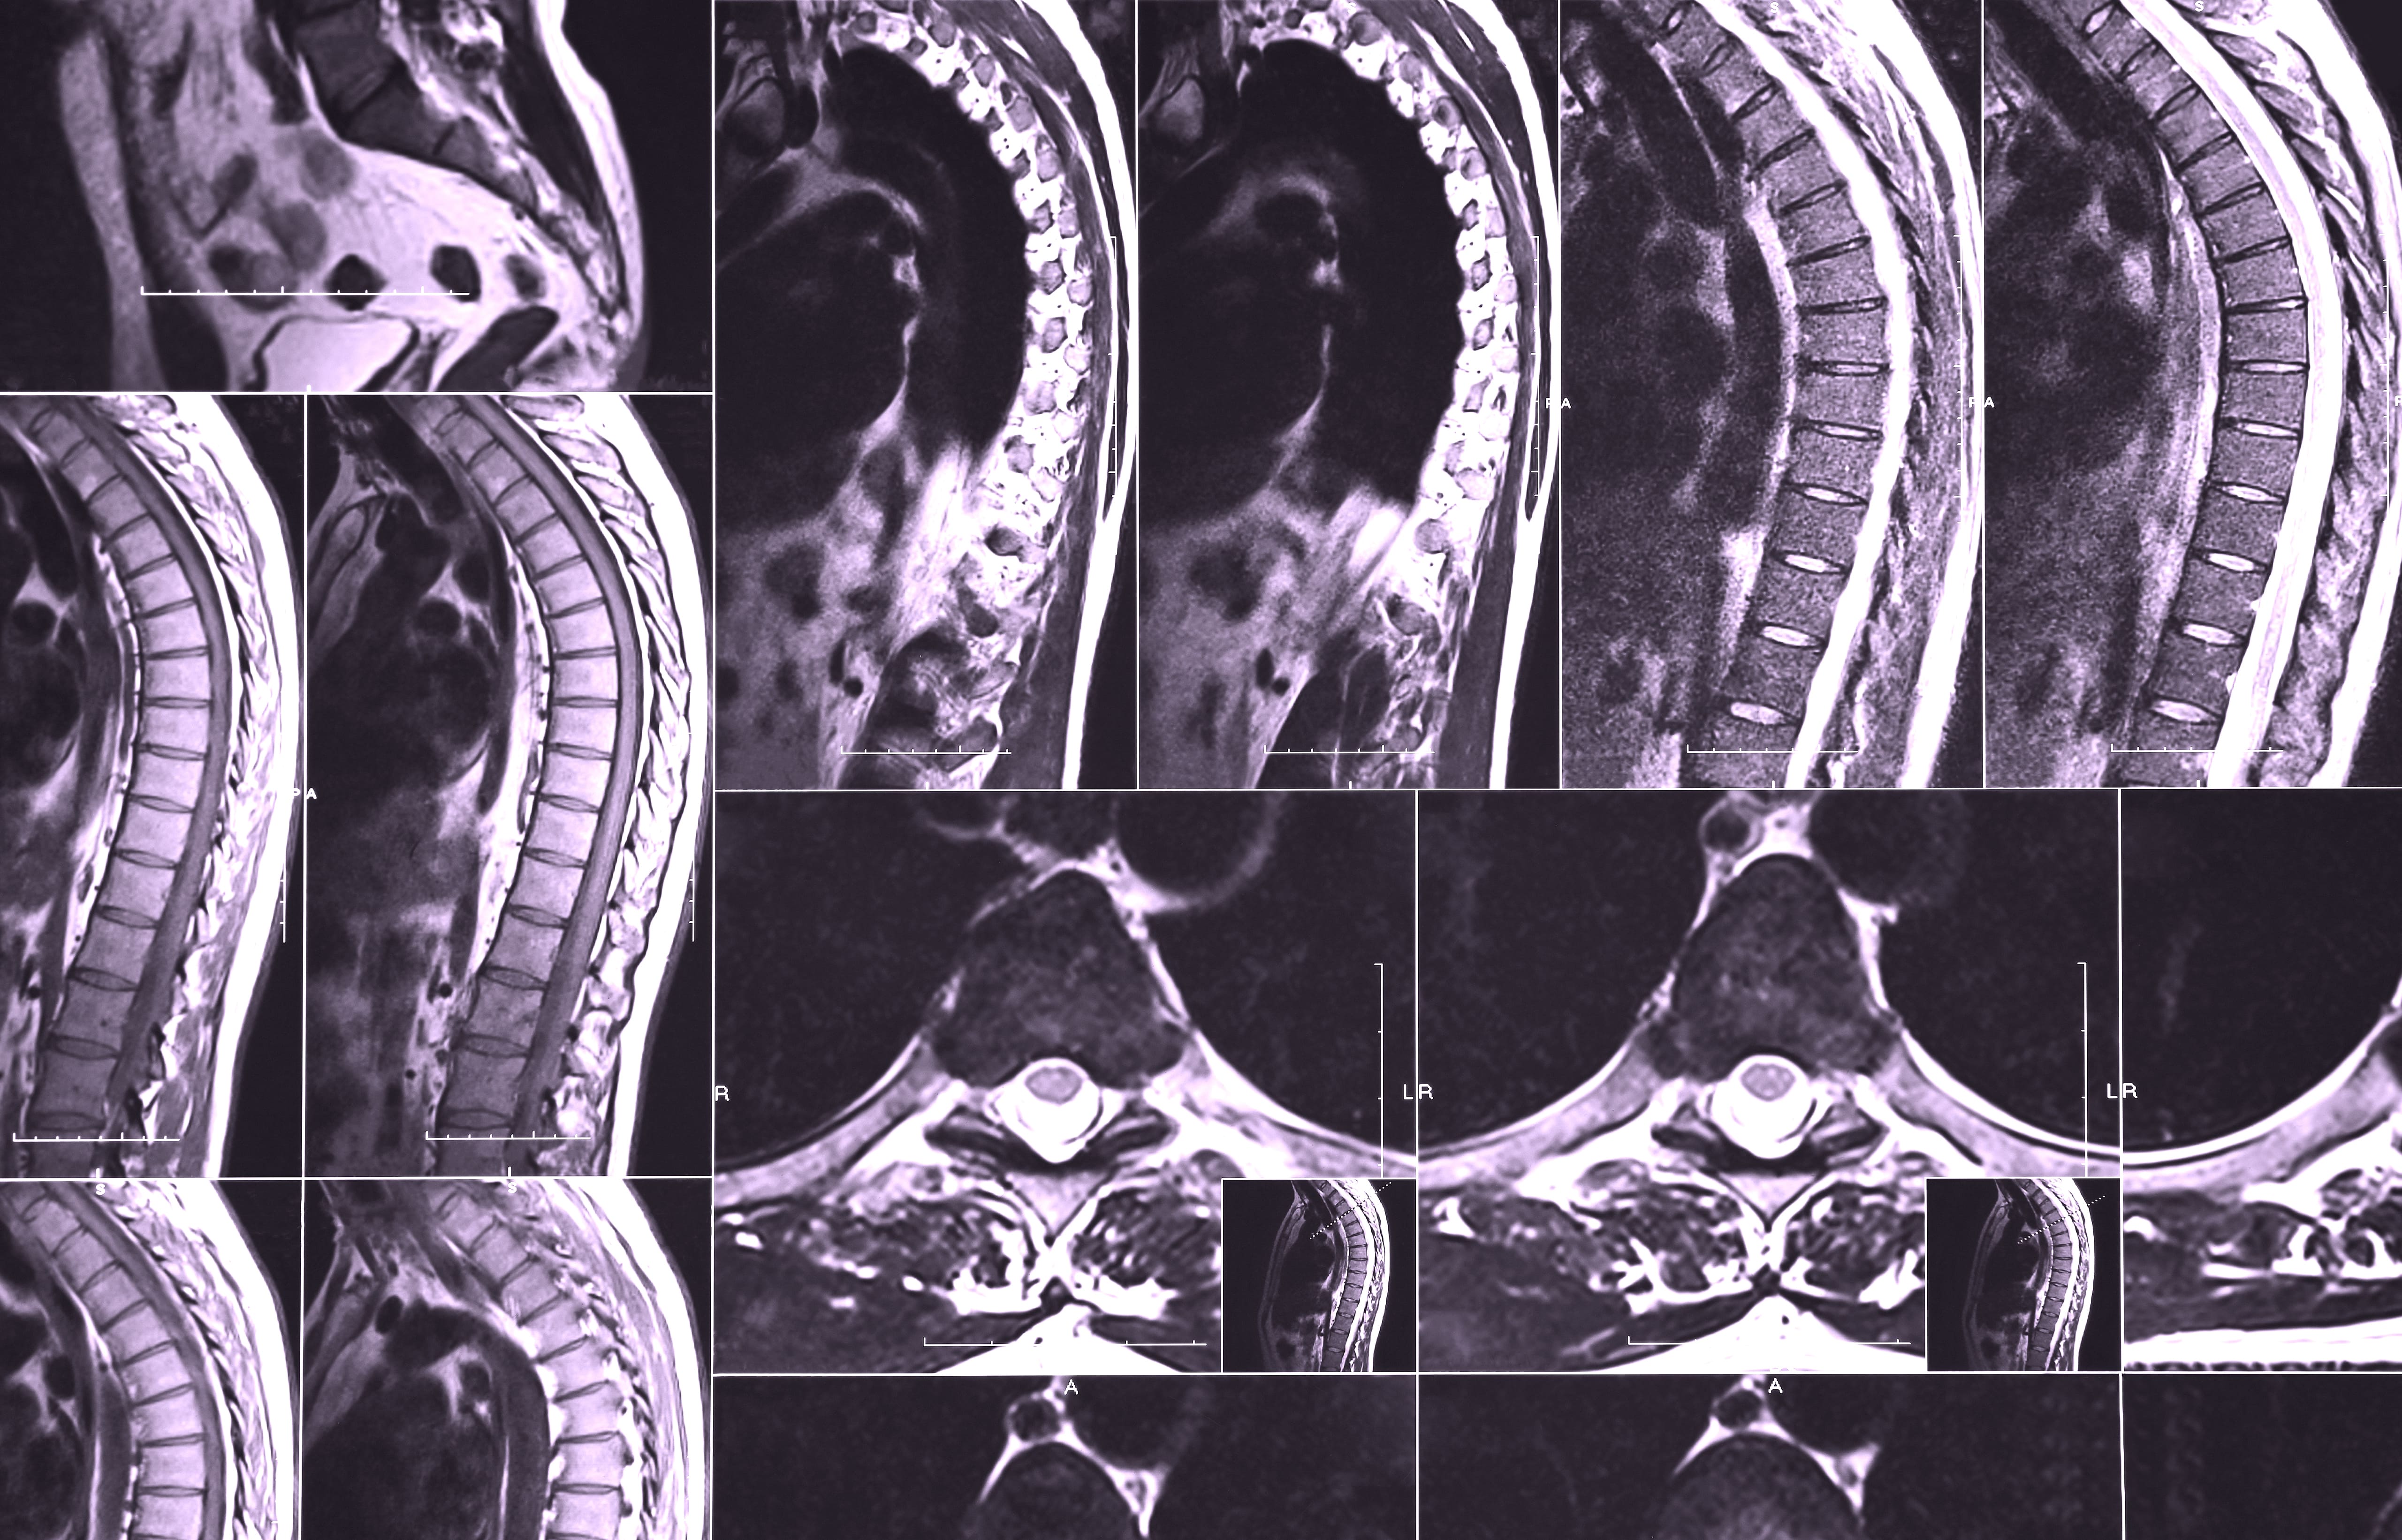

Den viktigaste diagnostiska metoden är en MR-undersökning (magnetkamera) av ryggmärgen . Med MR kan man tydligt se inflammationen inuti ryggmärgen, bedöma dess omfattning och nivå, samt utesluta andra orsaker till symtomen, såsom diskbråck eller tumörer som trycker på ryggmärgen. Detta är kritiskt för att snabbt kunna sätta in rätt behandling (ofta höga doser kortison) och begränsa bestående nervskador.